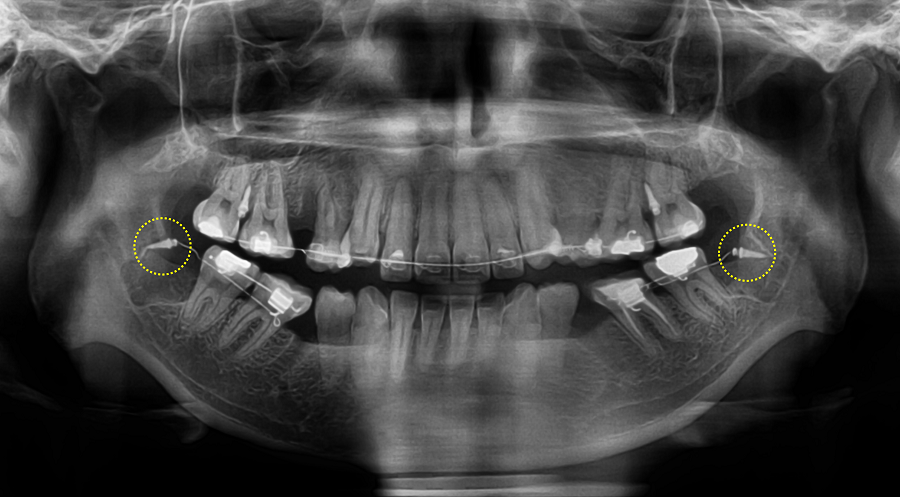

③ 미니스크류 기반 후방이동 — 이 케이스의 핵심 단계

대구치를 후방이동 시키기 위해 미니스크류를 식립해 안정적인 고정원으로 삼았습니다.

● 하악 양측 구치부

특히 하악은 핵심 포인트가 있습니다.

• 제2소구치가 심하게 설측 경사

• 그 공간으로 대구치가 전방으로 쓰러져 있음(tipping)

• 일반적으로 미니스크류를 가장 많이 식립하는 위치인 interradicular(치근 사이) 스크류 식립보다는

특별하게 **retromolar pad(하악 구치 후방 부위)**에 미니스크류를 식립했습니다.

이 부위에 스크류를 심으면 후방 견인과 치아의 직립에 매우 효율적입니다.

✔ 하악 대구치 후방이동 + 직립 완료

전방으로 쓰러져 있던 하악 제1대구치가 완전히 직립되고 후방으로 이동한 덕분에,

이후 보철(크라운) 제작 시 치근 방향과 일치하는 형태로 제작 가능해졌습니다.

쓰러진 치아가 계속 교합압을 받는 경우 치아에 좋지 않은 영향을 줄 수 있으므로, 이러한 치아의 직립은 큰 의미가 있습니다.